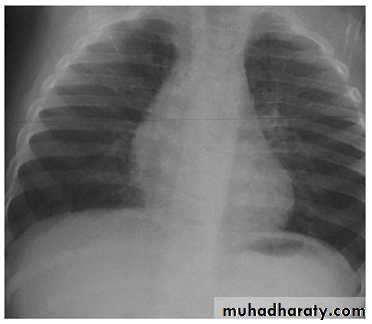

Q3/ A 4 years old child presented with history of high fever, chills, cough & dyspnea for the last 3 days. On examination of the chest found to have diminished air entry with course crepitation mainly involve lower right lung. WBC count 30,000/mm3.

• What is the diagnosis?

• What is other investigation support your diagnosis?

• What is the treatment?